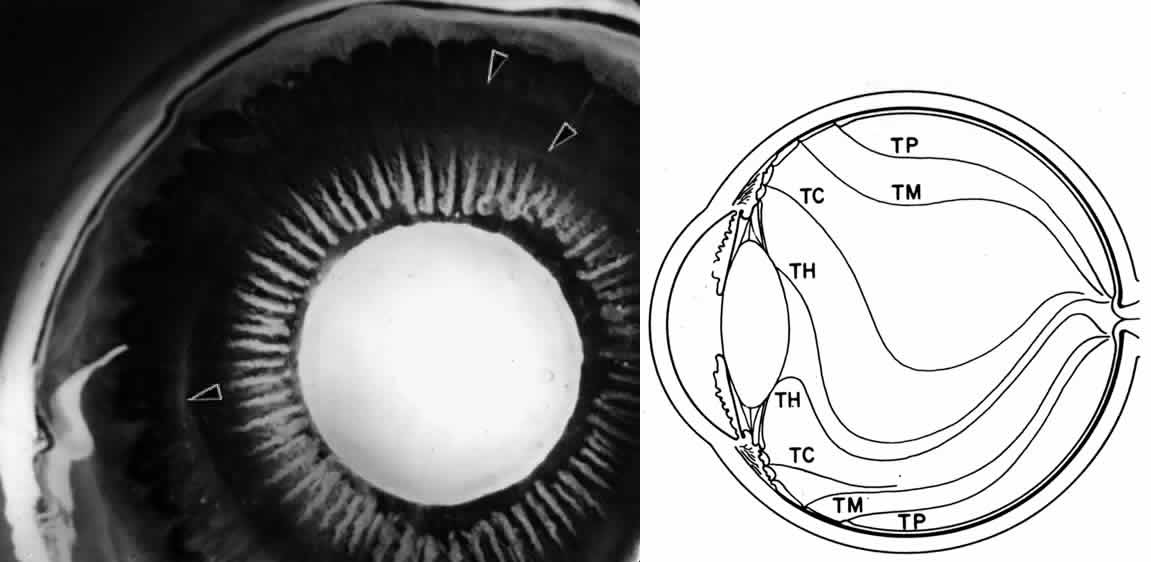

NONPIGMENTED CILIARY EPITHELIUM The ciliary epithelium consists of two layers: an inner nonpigmented (NPE) and

an outer pigmented layer (PE). These two layers derive from infolding

of the single cell layer of the optic vesicle against itself, to

form the optic cup. The potential space left between the two ciliary

layers rarely opens, owing to the frequency of junctional complexes

uniting the cells. A peculiar result of the infolding affects nomenclature

in this region, since the apices of the epithelial cells now face

each other across the potential space (Fig. 11). The bases of the cells face outward, toward the ciliary body stroma

for the PE, and toward the posterior chamber for the NPE. Basement membrane

covers the bases of both cell layers as is characteristic of epithelial

cells.  Fig. 11. Diagram showing the relationship of the two layers of ciliary epithelium. Basement

membrane (BM) covers their bases and their apices face each

other across a potential space. The cells are united by several types

of junctional complexes: 1, desmosomes; 2, gap junctions; and 4, puncta

adherentes. Onlythe apices of the nonpigmented epithelial cells (NPE) are

joined by “tight” junctions (3), composed of a zonula

occludens usually combined with a zonular adherens complex. PE, pigmented

epithelium. Fig. 11. Diagram showing the relationship of the two layers of ciliary epithelium. Basement

membrane (BM) covers their bases and their apices face each

other across a potential space. The cells are united by several types

of junctional complexes: 1, desmosomes; 2, gap junctions; and 4, puncta

adherentes. Onlythe apices of the nonpigmented epithelial cells (NPE) are

joined by “tight” junctions (3), composed of a zonula

occludens usually combined with a zonular adherens complex. PE, pigmented

epithelium.

The NPE of the ciliary body stretches in a continuous layer from the root

of the iris to the ora serrata. As the transition from pigmented iris

epithelium occurs, melanin granules in the inner layer suddenly decrease

in number, and the cells become slightly smaller (Fig. 12). In the pars plicata the NPE cells are cuboidal, 12 to 15 μm in width, with

central nuclei (Figs. 13A and 13B). The knobbiness that develops during aging is due to small nodular proliferations

of NPE cells, especially on the minor plicae (Fig. 13C). In the young eye the cells of the pars plana are also cuboidal, but

with growth they become thinner and more columnar, sometimes reaching

up to 30 μm in height and 5 to 10 μm in width (Fig. 13D). In the posterior half of the pars plana, some NPE cells tilt forward

as though responding to anterior zonular traction, while others may be

inclined posteriorly, suggesting complex vectors of force in this region. The

nuclei are vertically oval and lie near the apex of the cells. The

epithelium here becomes very irregular with aging, showing hyperplastic

toothlike cell processes intertwining and extending up into the

vitreous and among the zonular fibers. At the ora serrata the ciliary

NPE joins the retina abruptly, highlighting the difference in thickness

of these two layers (Fig. 14).  Fig. 12. Frontal view of a ciliary process at its junction with iris, showing conversion

to thicker, double-layered iris pigment epithelium (arrows). (Toluidine

blue, X 200) Fig. 12. Frontal view of a ciliary process at its junction with iris, showing conversion

to thicker, double-layered iris pigment epithelium (arrows). (Toluidine

blue, X 200)

Fig. 13. Ciliary nonpigmented epithelium. A. Anterior pars plicata, age 3. (hematoxylin-eosin, X 800) B. Posterior pars plicata with areas of thickened, pigmented

epithelium, age 3. m, ciliary muscle (hematoxylin-eosin, X 800) C. Nodular

proliferation of the nonpigmented epithelium appears

as small cellular caps over the surface at age 70. Z, zonule. (hematoxylin-eosin, X 400) D. Distorted epithelium of pars plana shows evidence

of traction in both anterior and posterior directions (adult). (hematoxylin-eosin, X 400) Fig. 13. Ciliary nonpigmented epithelium. A. Anterior pars plicata, age 3. (hematoxylin-eosin, X 800) B. Posterior pars plicata with areas of thickened, pigmented

epithelium, age 3. m, ciliary muscle (hematoxylin-eosin, X 800) C. Nodular

proliferation of the nonpigmented epithelium appears

as small cellular caps over the surface at age 70. Z, zonule. (hematoxylin-eosin, X 400) D. Distorted epithelium of pars plana shows evidence

of traction in both anterior and posterior directions (adult). (hematoxylin-eosin, X 400)

Fig. 14. Ora serrata in young adult, showing abrupt junction of ciliary nonpigmented

epithelium and sensory retina. A few hyalocytes are present in the

adjacent vitreous, and a degenerative cyst (C) is present in the peripheral

retina. (Toluidine blue, X 200) Fig. 14. Ora serrata in young adult, showing abrupt junction of ciliary nonpigmented

epithelium and sensory retina. A few hyalocytes are present in the

adjacent vitreous, and a degenerative cyst (C) is present in the peripheral

retina. (Toluidine blue, X 200)